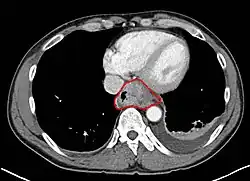

Anatomy

- Layers:

- Mucosa: epithelium, lamina propria, muscularis mucosa. Separated by basement membrane from rest of esophageal wall

- Submucosa: fibroelastic fibers, nervous plexuses, glands

- Muscularis propria: inner circular muscle layer, outer longitudinal muscle layer

- Adventitia: dense periesophageal connective tissue

- The serosa only lines the intra-abdominal esophagus

- Resectability often limited:

- Lack of fibrous serosa to prevent local spread

- Rich lymphatic network in submucosa and muscularis that allows longitudinal and circumferential drainage